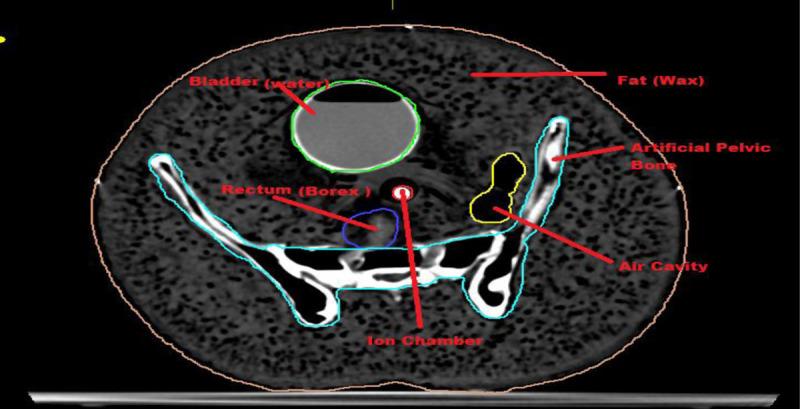

The analytical evaluation study was made by modifying the IMRT plan, subtracting the rectal volume from planning target volume (PTV), and applying the field-in-field technique in 3DCRT. Eight patients in various cervical cancer stages, from I‒III, were inducted for this investigation. The prescribed dose was 5000 cGy in 25 fractions. For all cases, both IMRT and 3DCRT plans were generated. For PTV and OARs, dose volume histogram (DVH) comparative analysis was carried out. For safety checks and quality control, pre-treatment verification of all the plans was performed using an indigenously developed pelvic phantom (for IMRT and 3DCRT) and gamma analysis with Delta4 phantom (for IMRT).

通过修改IMRT计划、从计划靶体积(PTV)中减去直肠体积并在3DCRT中应用射野内射野技术进行分析评估研究。纳入了8例处于I‒III期不同宫颈癌阶段的患者进行此项研究。处方剂量为25次分割照射共5000 cGy。对于所有病例,均生成了IMRT和3DCRT计划。对PTV和OARs进行了剂量体积直方图(DVH)对比分析。为进行安全检查和质量控制,使用自行研制的盆腔体模(用于IMRT和3DCRT)对所有计划进行了治疗前验证,并使用Delta4体模对IMRT进行了伽马分析。